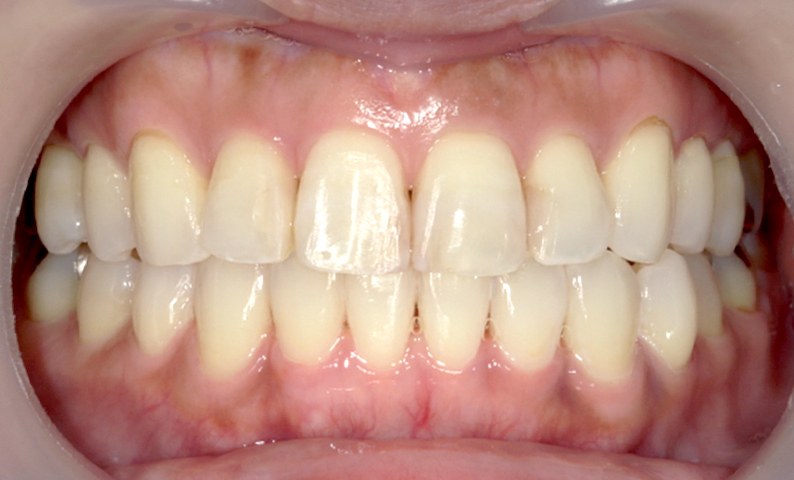

症例_002 前歯「捻転歯」症例

治療期間:10ヶ月金額:54万円+税30代女性少しのねじれ捻転歯前歯の突出感

| Before | After |

|---|---|

|